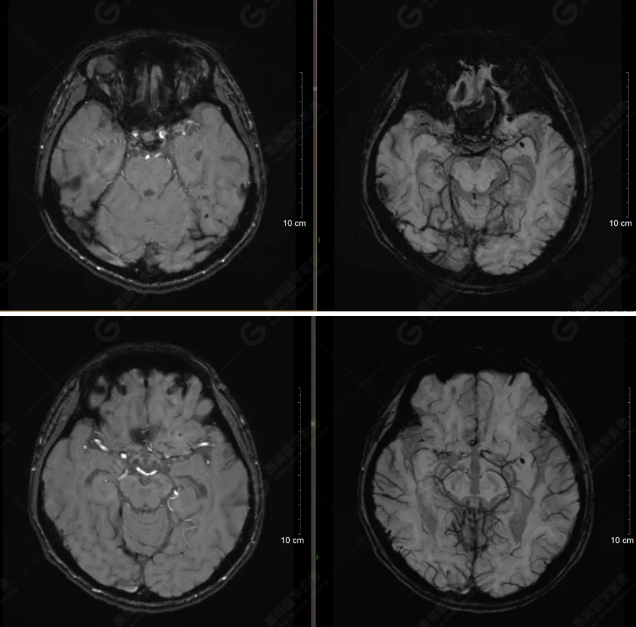

以下是平掃T2WI及FLAIR序列:

雙側(cè)大腦半球?qū)ΨQ,灰白質(zhì)對比正常,顱內(nèi)未見異常信號影。腦室系統(tǒng)未見擴(kuò)大,中線結(jié)構(gòu)居中。腦溝、裂未見增寬。幕下小腦、腦干未見異常。矢狀位示垂體形態(tài)、大小級信號未見異常。所示左側(cè)乳突內(nèi)見多發(fā)短T1長T2信號影。

顱腦MRI平掃未見明顯異常,左側(cè)乳突內(nèi)積血,建議補(bǔ)充SWI檢查。(左側(cè)為薄層原始圖像,右側(cè)為后處理5mm圖像)